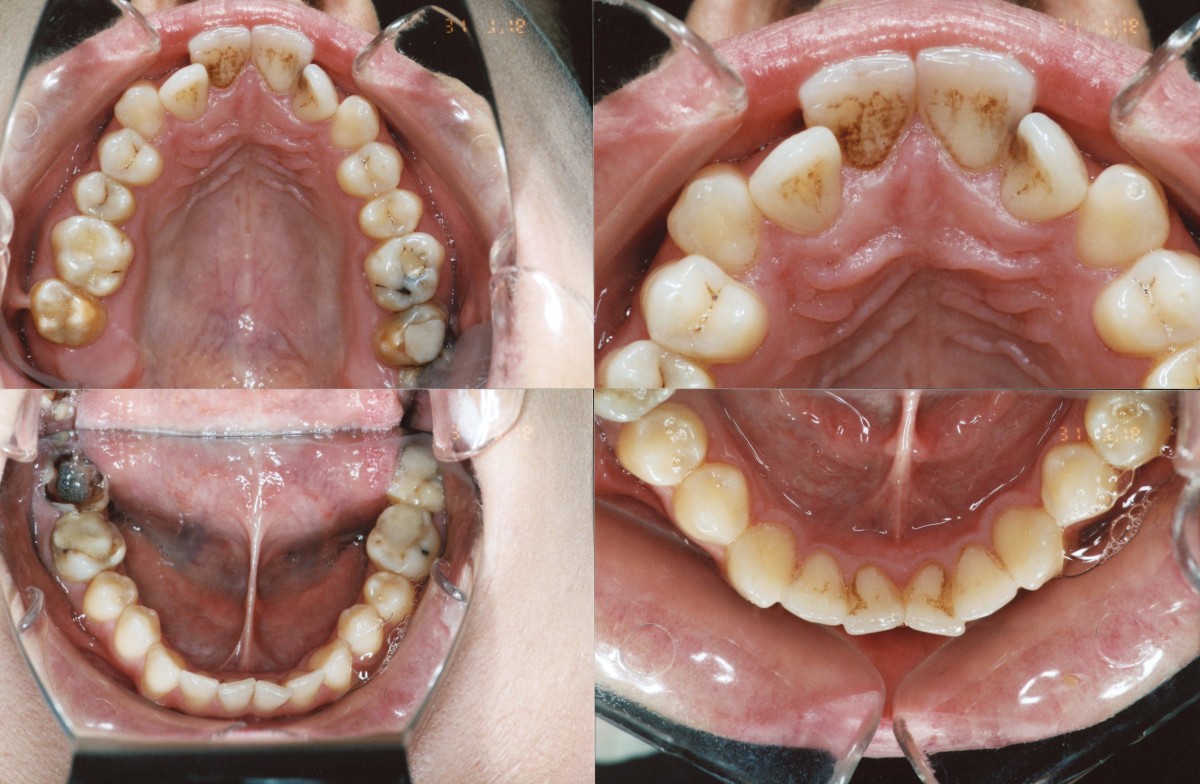

Pacient, 26 ani. Caz nonextracționist, Expander Maxilar + aparate ortodontice fixe bimaxilare.